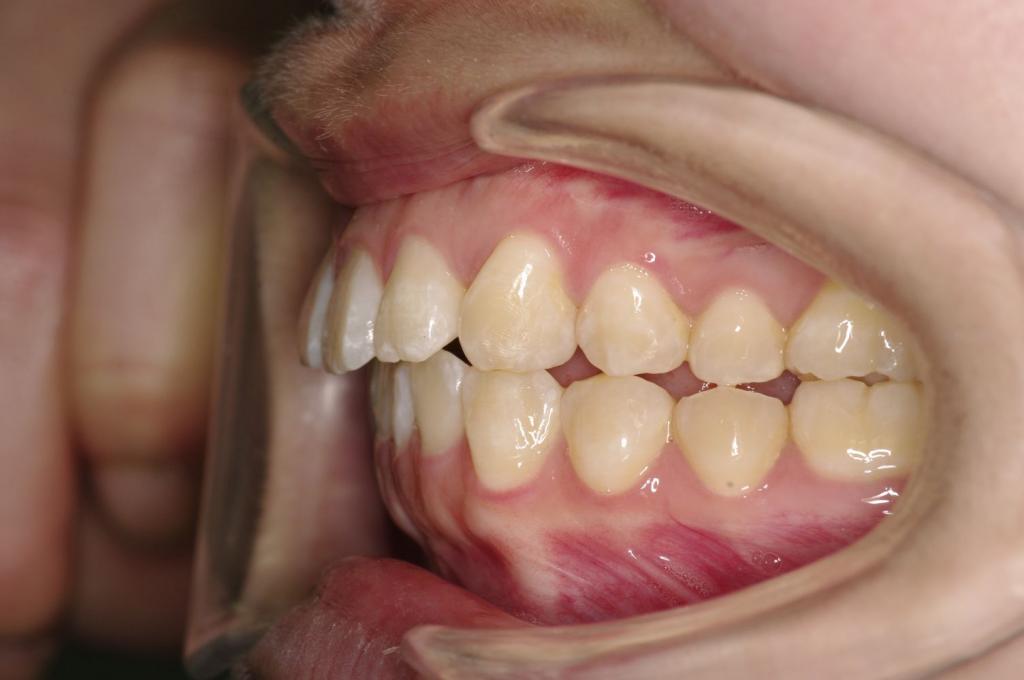

前歯、出っ歯・開咬の矯正治療

(治療期間、治療前後写真、治療方法、費用)WORKS